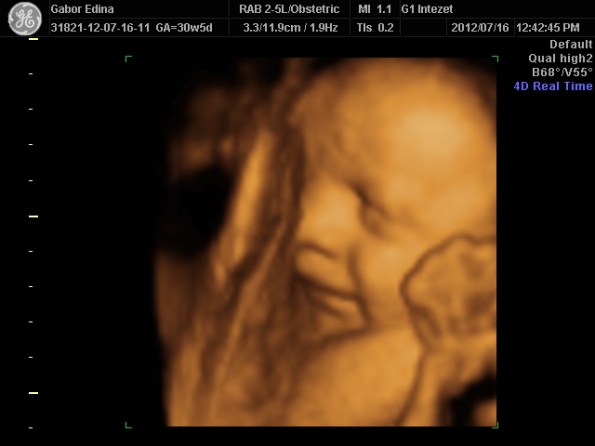

Zso: két baba után most fogalmam sincs Fancsa helyzetéről- most épp bugyi vonalban megy a motoszka, de mind a két oldalon... most nem érzek hüvelybe taposást... talán keresztben van??? vagy terpeszbe

31-én megyek uhu-ra... majd kiderül...